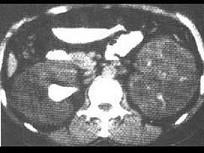

问题 下列哪项检查无助于诊断多囊肾 ( )

选项 A、同位素扫描 B、CT C、淋巴造影 D、B超 E、排泄性尿路造影

答案 C